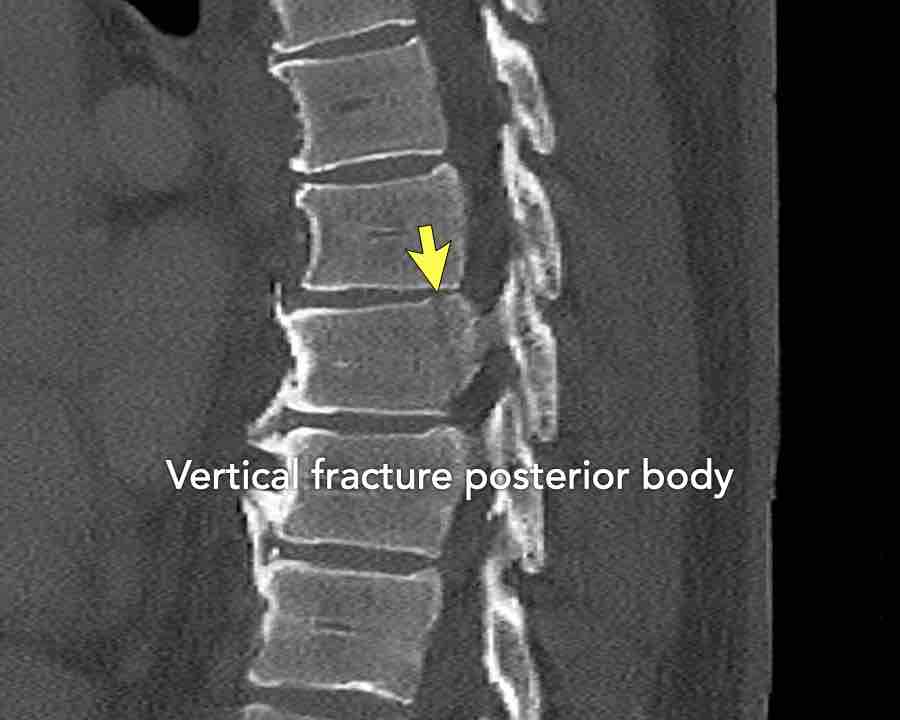

Findings

- Vertical fracture of the posterior border of the vertebral body. It looks a bit odd.

- Again we first have to look for the presence of a type C injury.

- Notice that there is a subtle posterior dislocation of the proximal levels. So this has to be C injury.

Conclusion

Injury type C + A3